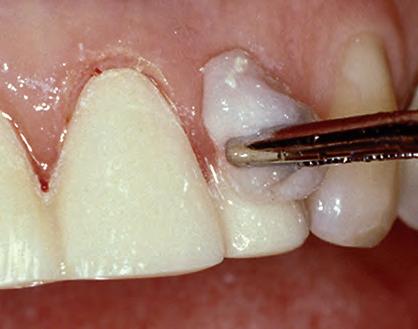

1. Subgingival preparation with bleeding. BLEEDING HEMOSTASIS

2. Scrub Astringedent™ X hemostatic firmly against bleeding tissues with Metal DentoInfusor™ tip.

CLEANING/TESTINGDISPLACEMENT

3. Firm air/water spray removes residual

and tests tissue for quality, profound hemostasis.

Remove

4. Soak Ultrapak™ knitted cord in Astringedent™ X hemostatic, pack, and leave for 5 minutes.